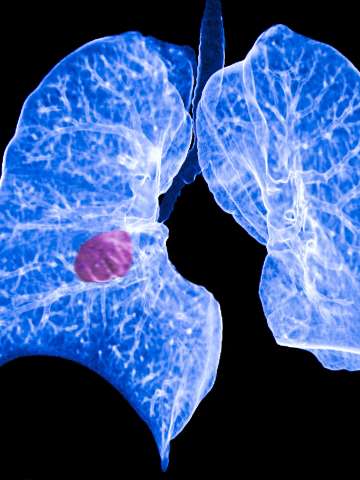

Lung cancer develops when abnormal cells in the lungs grow uncontrollably, forming tumors. At UCLA Health, we specialize in treating all kinds of lung cancer, including the two main types and rare forms of the disease.

Symptoms of lung cancer don’t usually appear until the disease has progressed. They include cough (sometimes coughing up blood), difficulty breathing, wheezing, chest pain and weight loss. The two main types of lung cancer are:

Comprehensive lung cancer screening

We focus on finding lung cancer at its earliest stages. Our pulmonary and thoracic physicians screen for lung cancer using the latest imaging techniques to detect lung nodules (spots) in patients who are at risk for developing lung cancer. This thorough screening process allows us to deliver a diagnosis as early as possible so treatments will be more effective.